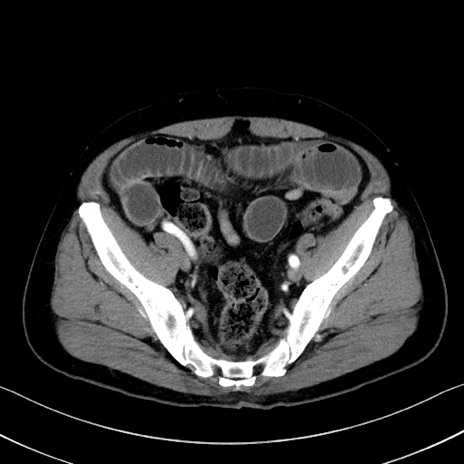

症例35(横断像)

【症例】70歳代 男性

【主訴】腹部膨満、嘔吐

【現病歴】昨日より腹部膨満感出現。本日増悪し、仙痛出現。嘔吐あり、受診。

【既往歴】糖尿病、胆摘後

【身体所見】BP 149/80mmHg、HR 74/min、BT 35.9℃、腹部:膨満、軟、圧痛なし。腸雑音減弱あり。上腹部正中切開瘢痕あり。

【データ】WBC 13500、CRP 1.72